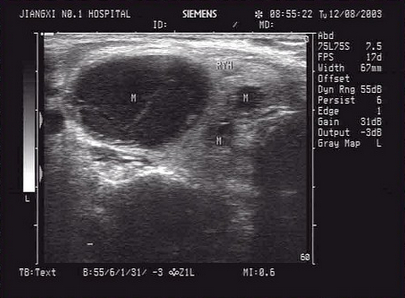

17、单项选择题

男,64岁,右上腹反复疼痛不适数10年,加重5天。声像图如图所示,诊断为()